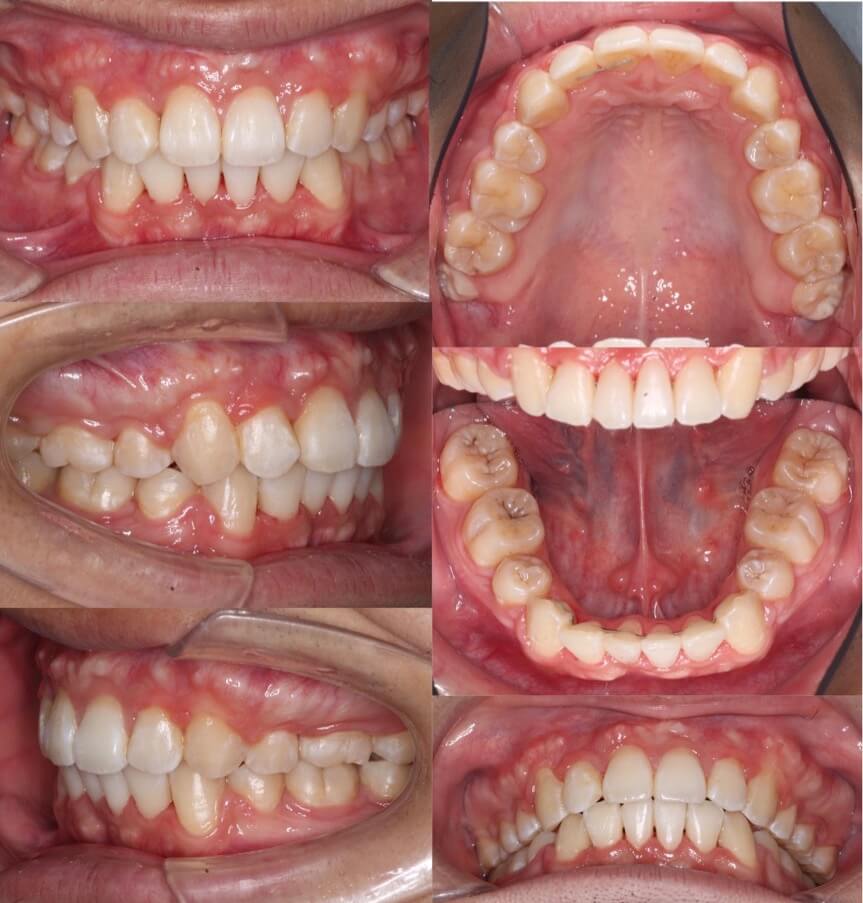

「美容目的にはリスクが伴う」

20代女性・マウスピース型装置・美容改善型

上の前歯の角度もE-lineも悪くはないのですが、患者さんは横顔での口元の突出感を改善したいということで、マウスピース型装置にて上下小臼歯抜歯矯正治療を行いました。美容目的要素が強くなるため、ほうれい線が深くなったり、ブラックとライアングルが増えるリスクについては事前によく説明しています。治療結果は前歯の後方移動量に対して横顔の変化量は少なめとなり、ちょうど良い形になりました。

<症例概要> 難易度:★★★☆☆

主訴:出っ歯・横顔の突出

年齢・性別:30代女性

住まい:千葉県船橋市

症状:軽度叢生・下顎前歯唇側傾斜

治療方針:抜歯空隙の閉鎖(中等度固定)

治療装置:マウスピース型矯正装置(アライナー装置)

抜歯:上下左右4番(計4本)

治療期間:1年6か月

アライナー枚数:47+30ステージ

リテーナー:上下クリアタイプ+フィックスタイプ

治療費用:990,000(税込)

代表的副作用:痛み・治療後の後戻り・歯根吸収・歯髄壊死・歯肉退縮